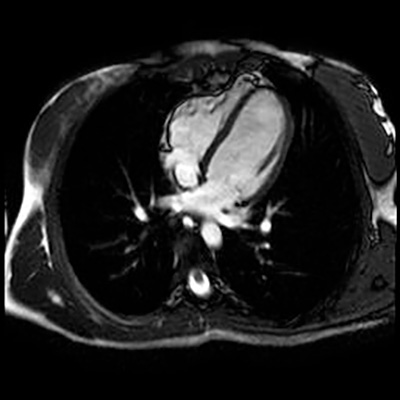

Es el estudio mediante RM del corazón tanto a nivel fisiológico como funcional. Ofrece una imagen detallada del corazón, incluidas las cavidades y las válvulas.

Ejemplo